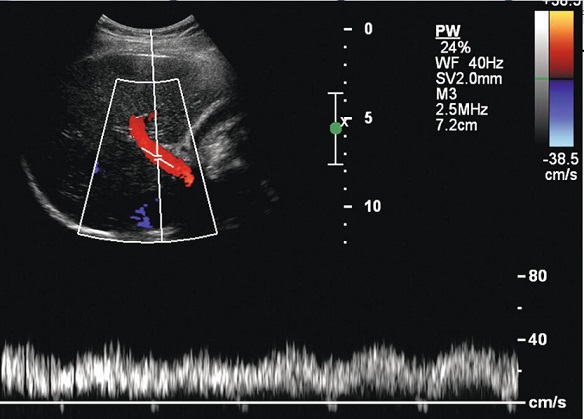

La flux sanguine de veine porte est mono-phasique

avec de nombreuse de frequence representees .

Normalement sa vitesse moyene > 10mm/s et vitesse

max est de > 18mm/s |